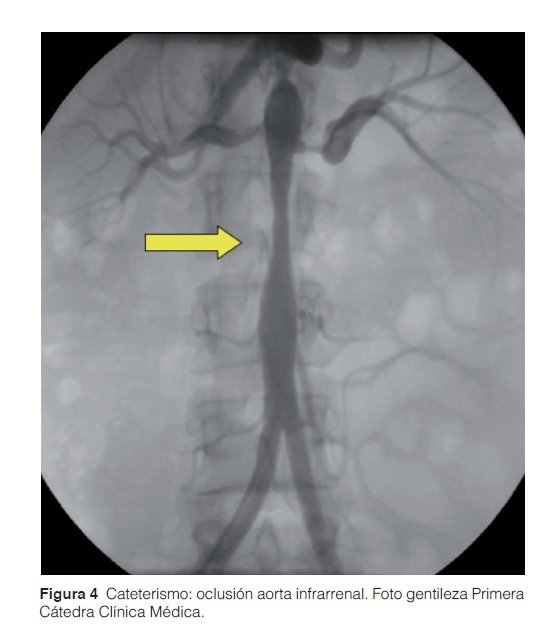

Se realizó cateterismo cardíaco donde se constató una estenosis del 60% en la aorta a nivel infrarrenal (Figura 4). A nivel del nacimiento de las arterias renales (Figura 5) se observó en el lado derecho una oclusión proximal del 95 % y en el lado izquierdo una oclusión del 95 % con buen lecho distal. Por esta razón se procedió a la colocación de tres stents autoexpansibles en dichos niveles. Con posterior normalización de cifras tensionales y mejoría clínica.